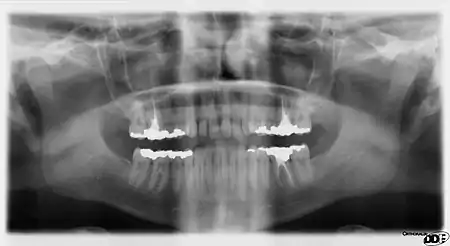

It is possible for both tooth decay and periodontal disease to be missed during a clinical exam, and radiographic evaluation of the dental and periodontal tissues is a critical segment of the comprehensive oral examination. The photographic montage at right depicts a situation in which extensive decay had been overlooked by a number of dentists prior to radiographic evaluation.